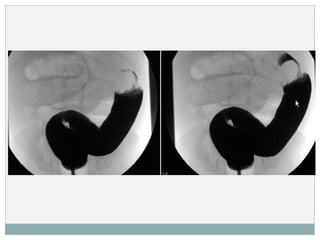

 ENEMA OPACO:

 Método diagnóstico – terapéutico.

 Signo del ‘muelle enrollado’

 1ª elección cuando hay diagnóstico claro ( Formas

típicas).

 REDUCCIÓN NO QUIRÚRGICA:

 Estables, invaginación ileo – cólica, No perforación.

 Reducción de la invaginación mediante enemas 

hidrostático ( suero o contraste) como neumático (aire),

guiados por US o RX.

 Ambas son aceptadas como técnica de reducción dependiendo del

profesional/ centro.

 La reducción guiada por US  enema hidrostático.

 Se ha observado que la reducción neumática tiene mayor tasa de

éxito. Menos complicaciones . Mayor tasa de recuperación en

complicaciones.

DIAGNÓSTICO (TÉCNICAS DE IMAGEN) ECO:  Método de elección.  S y E cercanas al 100%. VP – cercano al 100%.  Signo en ‘ojo de buey’ o ‘donut’.  Doppler: falta de flujo en la zona invaginada  ENEMA OPACO:  Método diagnóstico – terapéutico.  Signo del ‘muelle enrollado’  1ª elección cuando hay diagnóstico claro ( Formas típicas).

TRATAMIENTO  REDUCCIÓN NOQUIRÚRGICA:  Estables, invaginación ileo – cólica, No perforación.  Reducción de la invaginación mediante enemas  hidrostático ( suero o contraste) como neumático (aire), guiados por US o RX.  Ambas son aceptadas como técnica de reducción dependiendo del profesional/ centro.  La reducción guiada por US  enema hidrostático.  Se ha observado que la reducción neumática tiene mayor tasa de éxito. Menos complicaciones . Mayor tasa de recuperación en complicaciones.